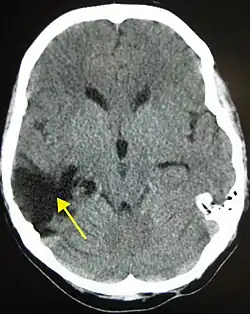

| CT scan showing cerebral contusions, hemorrhage within the hemispheres, and subdural hematoma. There is also displaced skull fracture of left transverse parietal and temporal bones.[2] | |